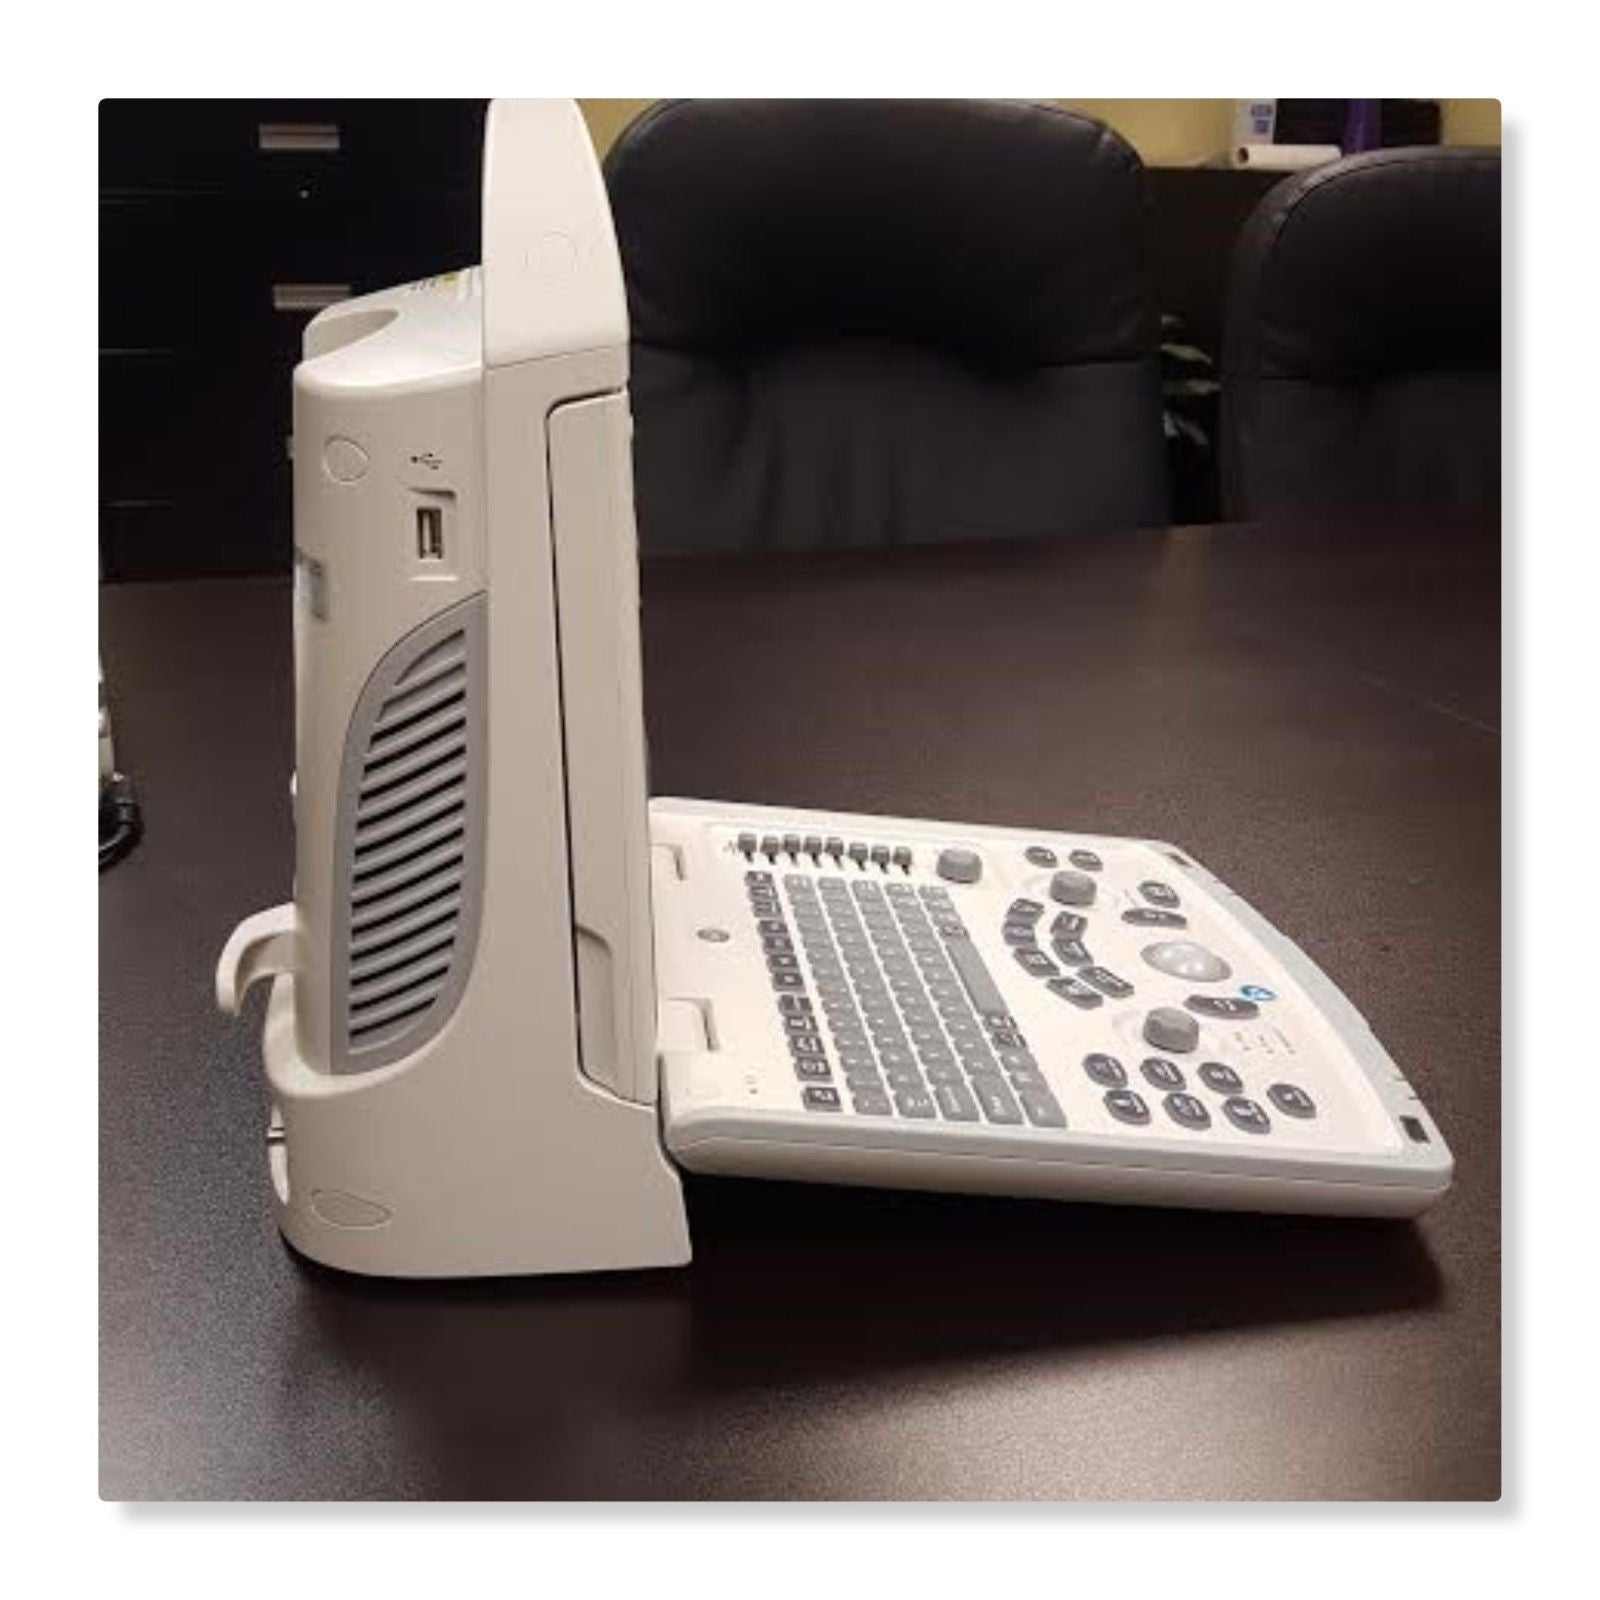

DIAGNOSTIC ULTRASOUND MACHINES FOR SALE

MINDRAY DIGITAL ULTRASOUND DIAGNOSTIC IMAGING SYSTEM,GREAT CONDITION(DP-50)

Sale price$ 5,250.00

Regular price$ 5,600.00

DIAGNOSTIC ULTRASOUND MACHINES FOR SALE

MINDRAY DP-50 PORTABLE ULTRASOUND WITH ONE CHOICE PROBE 1 YEAR WARRANTY

Sale price$ 5,998.00

Regular price$ 6,398.00

Save $ 676.00

DIAGNOSTIC ULTRASOUND MACHINES FOR SALE

MINDRAY DP-50 ULTRASOUND SYSTEM WITH ONE TRANSDUCER

Sale price$ 10,132.00

Regular price$ 10,808.00

DIAGNOSTIC ULTRASOUND MACHINES FOR SALE

Mindray DP-50 Ultrasound with Linear Transducer

Sale price$ 19,743.99

Save $ 170.00

DIAGNOSTIC ULTRASOUND MACHINES FOR SALE

Mindray DP50 Ultrasound with Convex Probe 35C50EA

Sale price$ 8,248.00

Regular price$ 8,798.00

Save $ 700.00

DIAGNOSTIC ULTRASOUND MACHINES FOR SALE

Mindray DP50 Ultrasound with Linear Array Probe 75L38EA

Sale price$ 10,498.00

Regular price$ 11,198.00